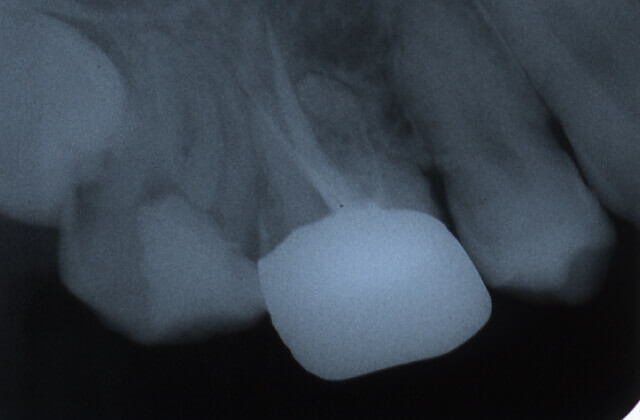

被せ物をした歯の違和感により来院されました

レントゲン写真により経過を確認します

黒い影は骨が溶け膿を持っている

黒い影が無くなり骨の再生が認められ経過は良好です